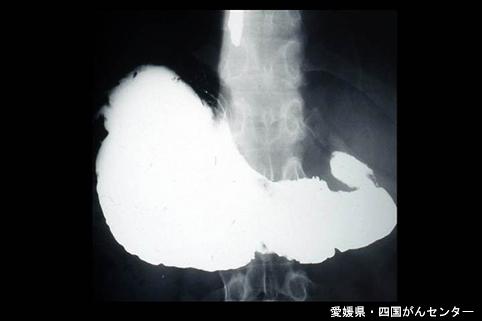

위 이소성 췌의 수술예(증례제시:아이치현, 국립병원 시코쿠 암센터, Dr.히라사키)

Ehime Pref., 시코쿠암센터 (Dr. 平崎)

[Image-ID:4962]

종양양 병변/이소성 점막

위(부위)/위각

X-P

40이상